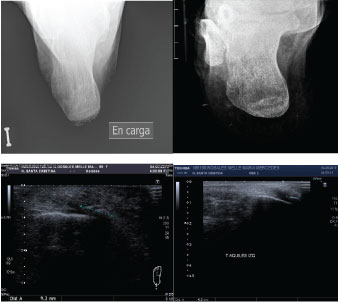

With regard to the change in millimeters (mm) of the calcification, all of the patients showed a decrease in the size of calcification. The radiological change in Achilles CT was significant; decreased from 10 ± 5.3 to 5.3 ± 5.22 mm (p = 0.0186), (Table 2, Figures 2, Figure 3, Figure 4, Figure 5 and Figure 6).

Figure 2: Case 1: In a 50-year-old female, after 10 sessions of treatment, pain decreased from 8/10 to 1/10 and size of calcification decreased from 12 to 6 mm. View Figure 2

Figure 3: Case 2: In a 38-year-old female, after 20 sessions of treatment, pain decreased from 10/10 to 2/10 and size of calcification decreased from 3 to 2 mm. View Figure 3